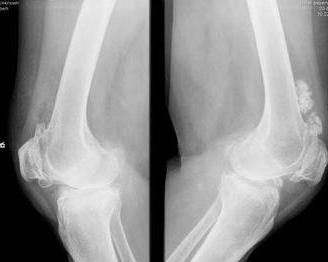

骨膜软骨瘤亦叫骨皮质旁软骨瘤,是源于骨膜或骨膜下结缔组织的一种良性软骨瘤。1952年Lichtenstein和Hall首先报道这一肿瘤。